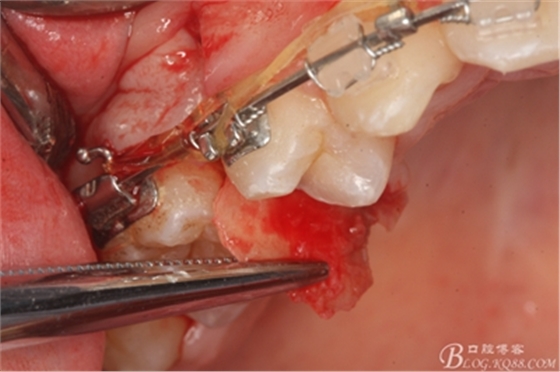

圖11.仔細(xì)考慮之后,在14頰側(cè)做垂直切口,切口長(zhǎng)度僅達(dá)膜齦聯(lián)合處,做小切口。

圖12. 做垂直切口+齦溝內(nèi)切口,形成角形瓣,暴露出15根面。

圖13. 用小球鉆去除約1mm牙槽骨,暴露15牙根面約5mm。